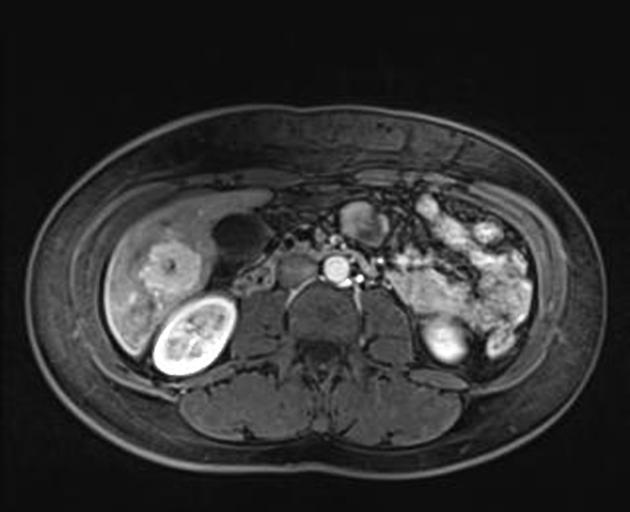

Магнитно-резонансная томография при нодулярной гиперплазии печени выявляет следующие анатомические признаки:

На Т1-взвешенных изображениях определяется образование с изоинтенсивным или слегка гиперинтенсивным сигналом по отношению к окружающей паренхиме печени, что свидетельствует о высоком содержании клеточных элементов.

На Т2-взвешенных изображениях визуализируется образование с преимущественно изоинтенсивным сигналом, при этом центральный рубец даёт слабовыраженный гиперинтенсивный сигнал.

В режиме динамического контрастного усиления определяется выраженное раннее артериальное накопление контраста в узле с последующим равномерным вымыванием на венозной и поздней фазах.

В режиме диффузионно-взвешенной визуализации фиксируется свободная диффузия в пределах узла без выраженного ограничения, что отличает доброкачественный характер нодулярной гиперплазии.